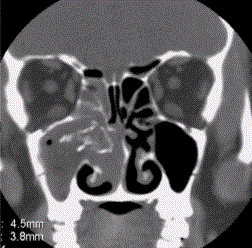

问题 患者男,35岁,鼻腔分泌物多,流脓涕,鼻塞,头痛,面部局部压痛1个月余。体检:鼻腔分泌物多,鼻黏膜肿胀。CT表现如下图。 慢性化脓性鼻窦炎影像学表现包括

选项 A.鼻甲肥大 B.窦腔透过度减低 C.窦腔内积液 D.鼻窦黏膜增厚 E.窦壁骨质硬化增厚 F.病变呈长T1短T2信号影

答案 ABCDE